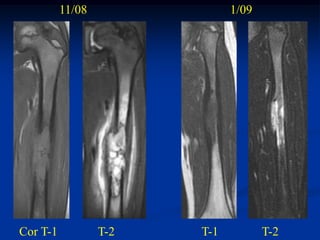

Case #417.2

10/08                  11/08           12/08

6 year male with pain in thigh for 1 mo.

11/08               1/09

Cor T-1           T-2   T-1          T-2